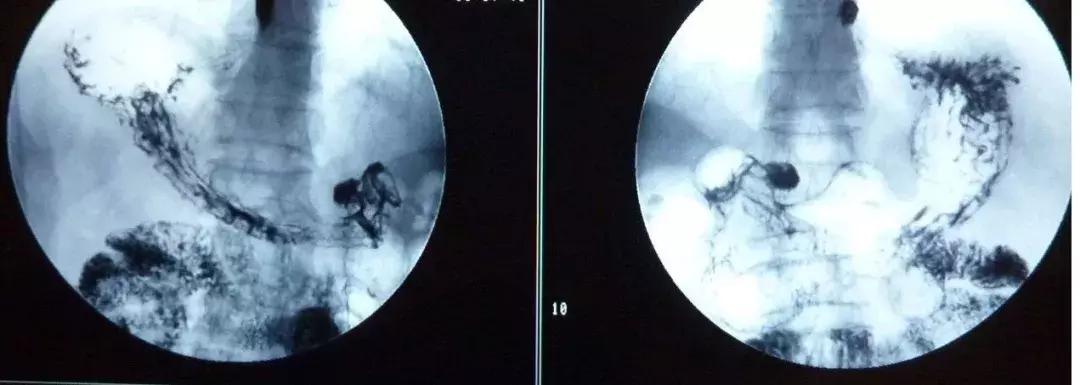

如果患者需要进行上消化道检查,但因有严重心脑血管疾病、呼吸功能障碍、严重贫血状况等情况,无法进行消化道内镜检查,还可以选择其他方式,比如做钡餐、碘水造影和腹部CT等,同样有助于筛查上消化道肿瘤。